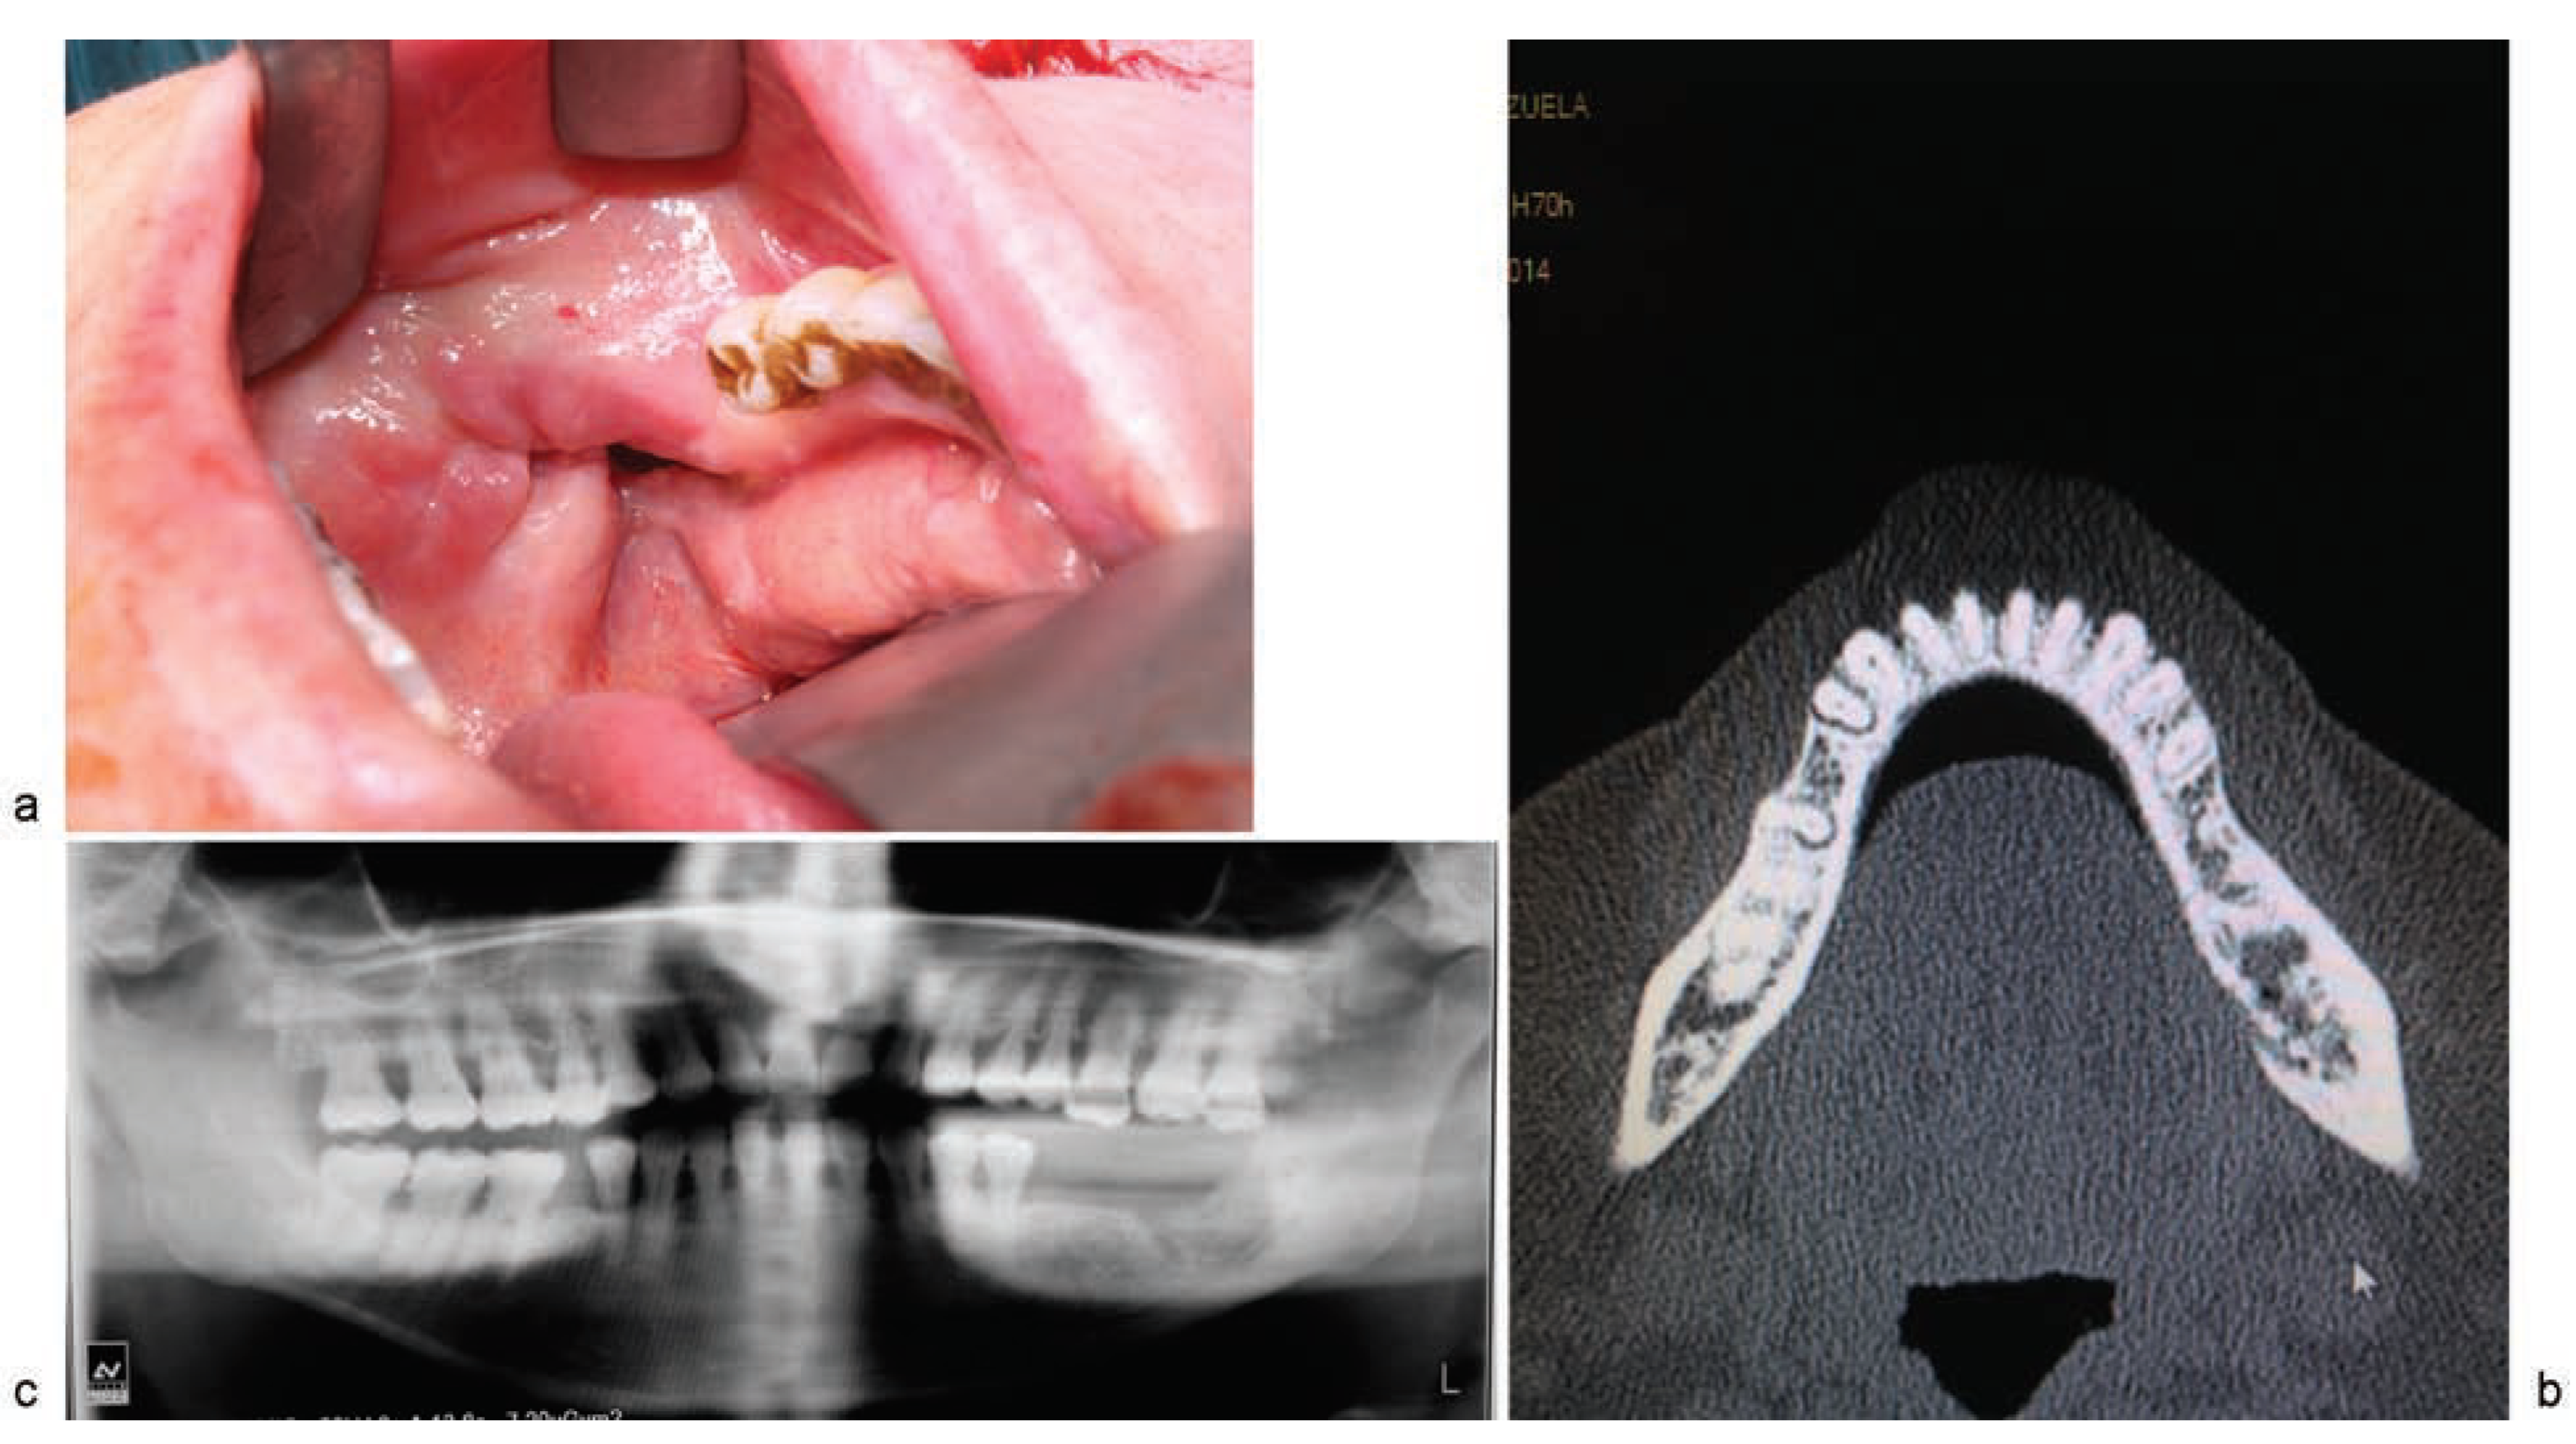

Clinical Cases